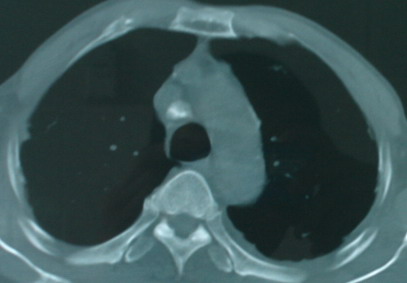

以下是引用医影拾贝在2008-6-3 18:48:00的发言:[br]双上肺弥漫性小结节影,纵隔窗内钙化淋巴结影,考虑血播性tb可能性较大,不除外肺ca可能

以下是引用卜一在2008-6-3 19:33:00的发言:[br]双肺结节,以双上肺分布为多,期间搀杂片状致密影及索条致密影。考虑:继发性肺结核伴血型播散可能性大。不除外肺泡ca的可能!另:椎体退变!

以下是引用panyishengct在2008-6-3 21:09:00的发言:[br]双上肺弥漫性小结节影,纵隔窗内钙化淋巴结影,考虑矽肺或/和tb可能性较大,不除外肺ca可能。腰椎考虑退变。 [br][br]